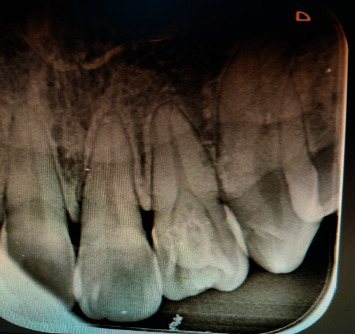

形态发育异常在上颌侧切牙中很常见,但在一颗牙齿中同时出现两种发育异常的情况却相对少见。在本病例报告中,我们介绍了一例在左侧切牙中同时出现爪状尖牙和内陷牙的病例。此类病例的早期诊断和及时治疗对于防止任何不良后果的发生非常重要。

Morphogenic developmental anomalies are common in maxillary lateral incisors, but simultaneous occurrence of two developmental anomalies in a single tooth is relatively uncommon. In this case report, we present a case of cooccurrence of the talon's cusp with dens invaginatus in the left lateral incisor tooth. Early diagnosis and prompt treatment of such cases are important to prevent any untoward consequences.